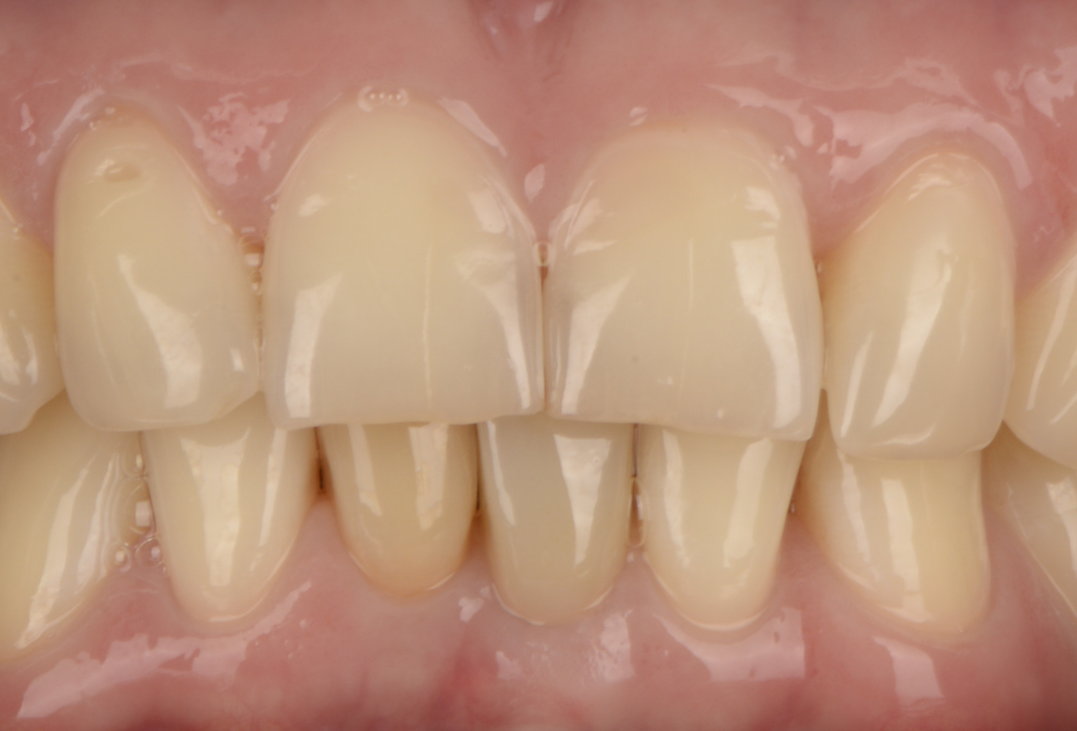

Навігаційна імплантація з кістковою та м'якотканинною пластикою

Жінка, 42 роки

Відсутність жувального зуба на нижній щелепі, виражена атрофія кісткової та м'яких тканин, порушення жувальної функції та естетики.